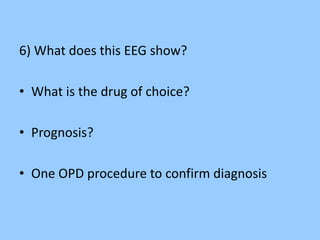

1. The document discusses EEG patterns and findings in various neurological conditions seen in children. It includes descriptions of normal EEG findings as well as abnormal patterns seen in conditions like absence seizures, West syndrome, benign childhood epilepsy with centrotemporal spikes, Lennox-Gastaut syndrome, non-convulsive status epilepticus, subacute sclerosing panencephalitis, and herpes encephalitis.

2. Case studies are presented with clinical histories and EEG findings to illustrate different pathologies. Treatment options are also mentioned for many of the conditions.